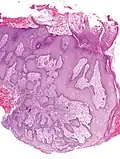

Microscopic image of the epidermis, which constitutes the outer layer of skin, shown here by the white bar

Microscopic image showing the layers of the epidermis. The stratum corneum appears more compact in this image than above because of different sample preparation.

The epidermis is the outermost of the three layers that comprise the skin, the inner layers being the dermis and hypodermis.[1] The epidermal layer provides a barrier to infection from environmental pathogens[2] and regulates the amount of water released from the body into the atmosphere through transepidermal water loss.[3]

The epidermis is composed of multiple layers of flattened cells[4] that overlie a base layer (stratum basale) composed of columnar cells arranged perpendicularly. The layers of cells develop from stem cells in the basal layer. The thickness of the epidermis varies from 31.2 μm for the penis to 596.6 μm for the sole of the foot with most being roughly 90 μm. Thickness does not vary between the sexes but becomes thinner with age.[5] The human epidermis is an example of epithelium, particularly a stratified squamous epithelium.